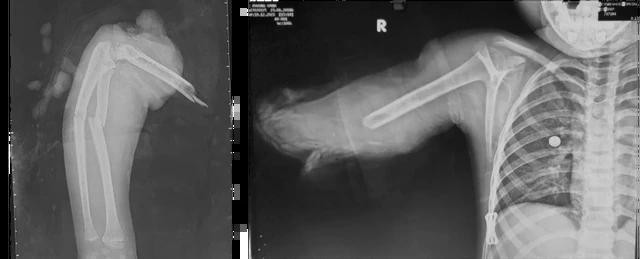

| Bé gái được đưa đến bệnh viện trong tình trạng đứt lìa một phần cánh tay |

Lúc nhập viện bé tỉnh táo, hơi tái xanh, vết thương đứt lìa dạng vặn xoắn ở 1/3 dưới cánh tay phải, mô mềm dập nhiều vát chéo lên đến 1/3 giữa trên; gãy 2 xương cẳng tay.

Kết quả chụp X-quang và chẩn đoán xác định bé gái bị gãy 2 xương cẳng tay phải, đứt lìa 1/3 giữa dưới cánh tay phải. Ngoài ra, bé gái còn có vết thương mặt lưng cẳng tay phải.

Ở phòng mổ 1, các bác sĩ làm sạch phần cánh tay bị đứt lìa. Kết hợp xương 2 xương cẳng tay bị gãy bằng phương pháp xuyên đinh nội tủy dưới màn tăng sáng.

Phần cánh tay bị lìa sau đó được chuyển ngay sang phòng mổ 1 để nối vi phẫu cho em bé. Các bác sĩ nhanh chóng cắt ngắn xương, cắt gọn bề mặt xương cánh tay, kết hợp xương cánh tay bằng 2 đinh xuyên nội tủy và khâu nối vi phẫu động mạch cánh tay, tĩnh mạch, thần kinh quay, trụ, giữa, khâu các gân cơ, giải ép khoang…